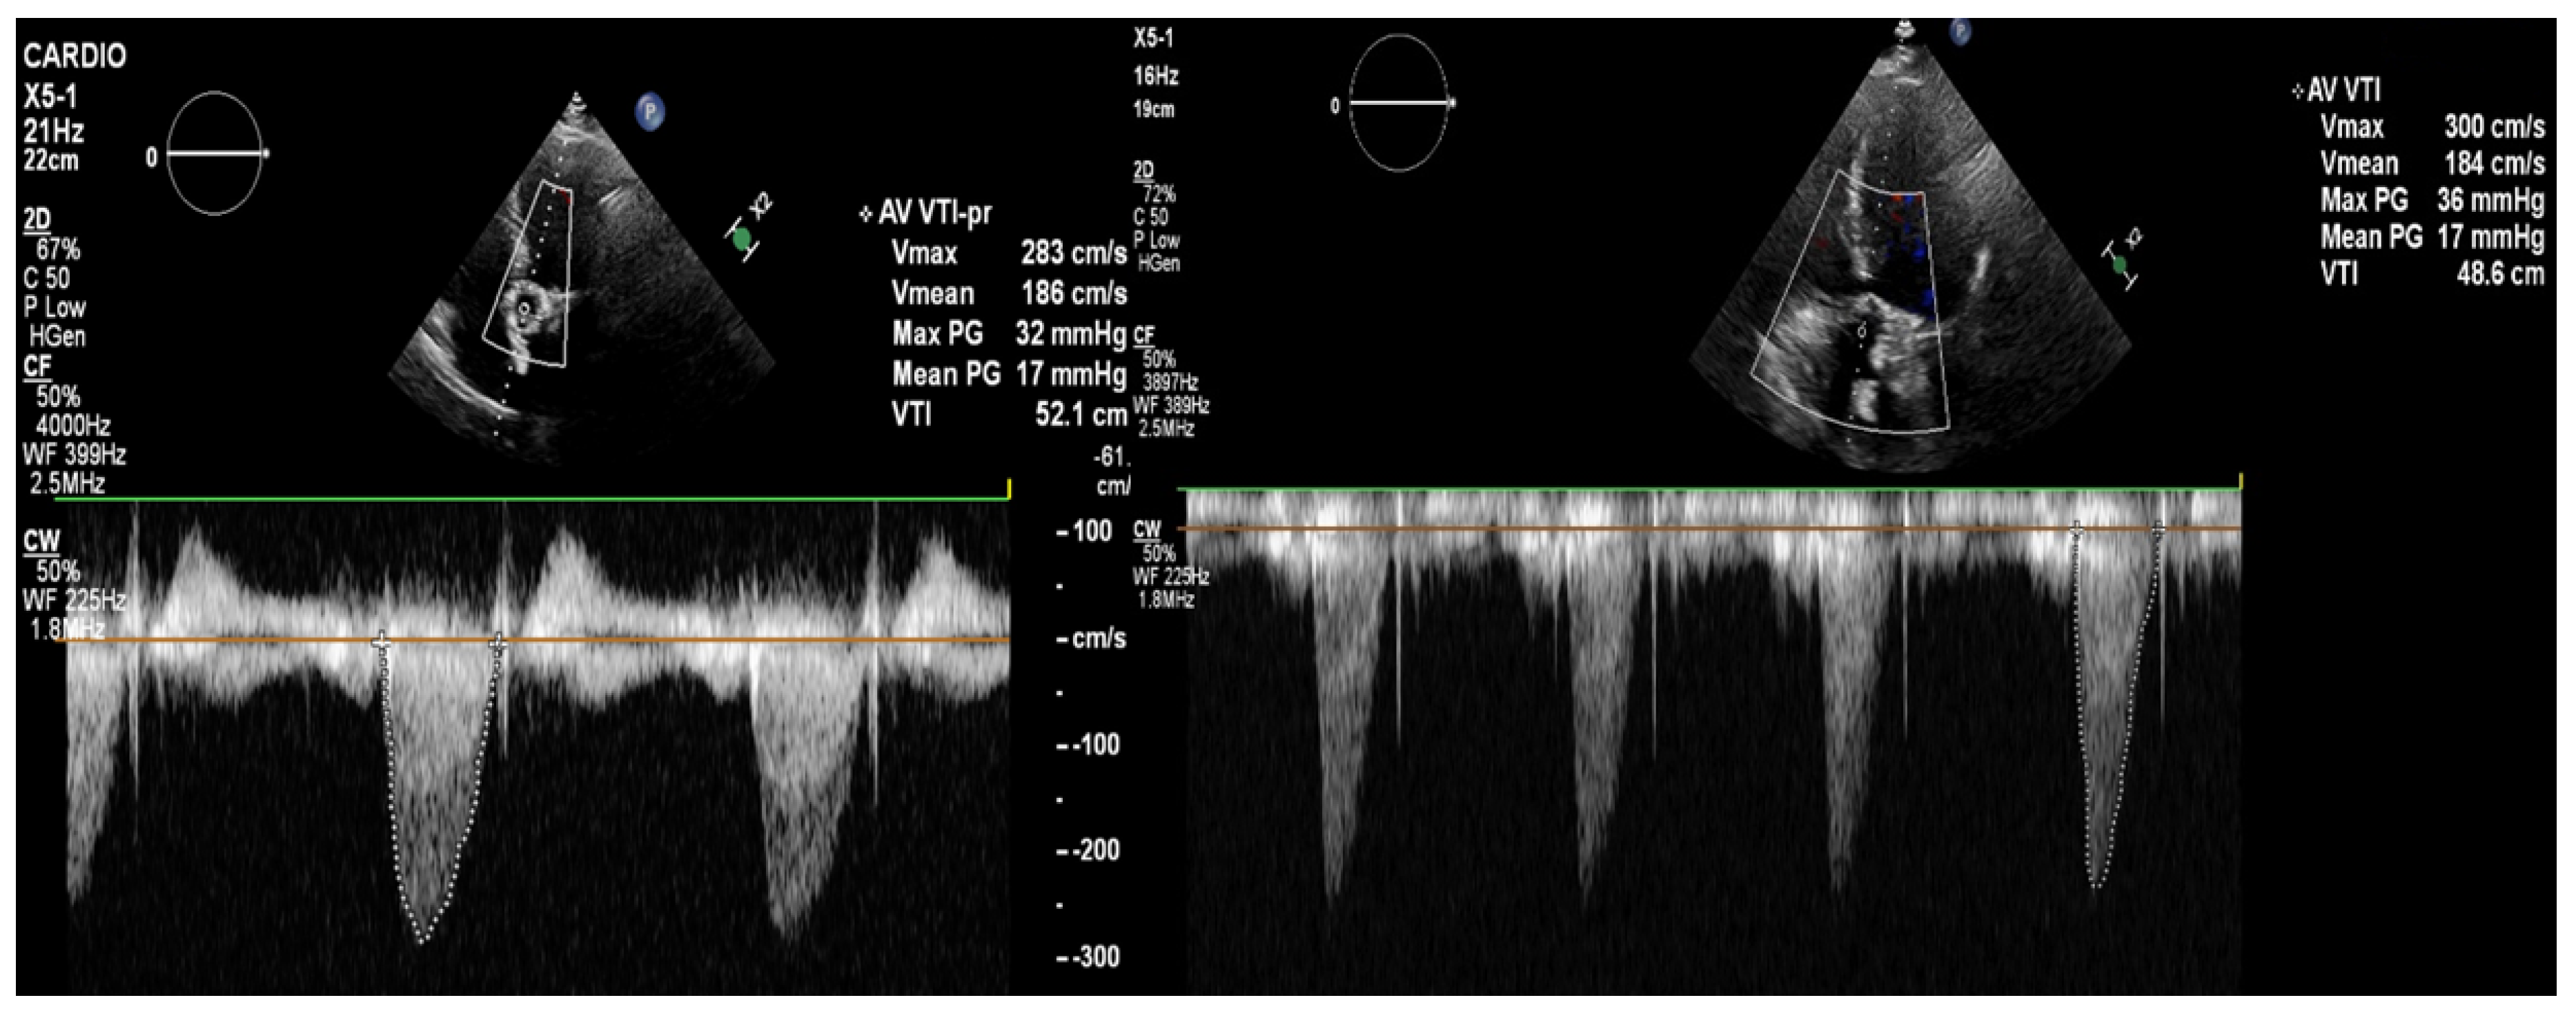

The transthoracic echocardiography showed a reduction in the gradients through the aortic valve prosthesis with parameters similar to that after the TAVI (on left: post-TAVI; on right: post-LMWH treatment). According to the 2021 ESC/EACTS Guidelines, in patients after TAVI, lifelong SAPT is recommended in the lack of indications for oral anticoagulants (OACs) [1]. However, despite similar recommendations for aspirin, the 2020 ACC/AHA Guidelines suggest that in patients with a low bleeding risk, it is worth acknowledging the antithrombotic prophylaxis with DAPT or VKA [2]. The direct-acting oral anticoagulants (DOACs) were not found to be superior to the administering antiplatelet or VKA, and in patients without indications for OAC, were linked to a higher incidence of all-cause mortality [3,4,5]. The 2021 ESC/EACTS and 2020 ACC/AHA Guidelines for managing valvular heart disease indicate that anticoagulation using VKAs or UFH is a first-line therapy for bioprosthetic valve thrombosis. Such an approach is highly effective in the normalization of valve function in 85% of the patients [6].